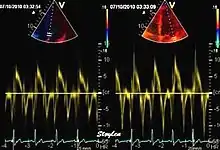

Like Doppler flow, tissue Doppler can be acquired both by spectral analysis (spectral density estimation) as pulsed Doppler[1] and by the autocorrelation technique as colour tissue Doppler[2] (duplex ultrasonography). While pulsed Doppler only acquires the velocity at one point at a time, colour Doppler can acquire simultaneous pixel velocity values across the whole imaging field. Pulsed Doppler on the other hand, is more robust against noise, as peak values are measured on top of the spectrum, and are unaffected of the presence of clutter (stationary reverberation noise).

Colour tissue Doppler

Unlike spectral Doppler, colour tissue Doppler samples velocities from all points of the sector, by shooting two pulses successively, and calculating the velocity from the phase shift between them by autocorrelation. The calculation is slightly different from the true Doppler effect, but the result becomes identical. This results in a single velocity value per sample volume. The result is a velocity field of (nearly) simultaneous velocity vectors towards the probe. The advantage of colour Doppler over spectral Doppler is that all velocities can be sampled simultaneously. The disadvantage is that if there is clutter noise (stationary reverberations), the stationary echoes will be integrated in the velocity calculation, resulting in an under estimate. As pulsed wave Doppler are displayed as a spectrum, the colour Doppler values will correspond to the mean of the spectrum (in the absence of clutter), giving slightly lower values. In the HUNT study, the difference in peak systolic values were about 1.5 cm/s.[26]